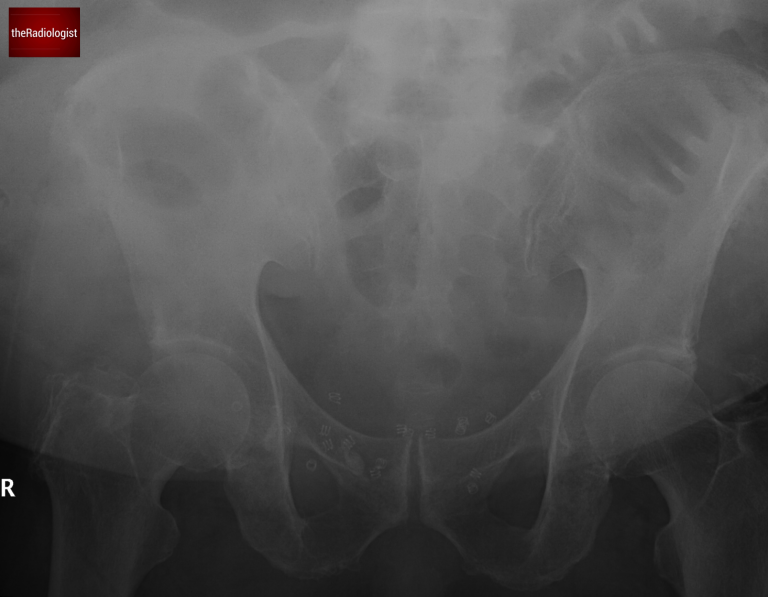

A female in her 60s presents with lower abdominal pain and absolute constipation. Here is her abdominal X-Ray (two separate images):

Abdominal X-Ray on presentation: image 2

This abdominal X-Ray a difficult film to assess as it is split into two but we can see dilated bowel loops. Let’s have a look at this table below which helps us differentiate between large and small bowel obstruction.

In this case instead of valvulae conniventes traversing the whole wall of the bowel which we with small bowel, we can see haustrae which we can just see at the periphery of the bowel lumen. This along with the degree of distension points us towards mechanical large bowel obstruction.

We can see haustrae which do not traverse the whole bowel wall rather than valvulae conniventes within small bowel which do – this points to large bowel dilatation.